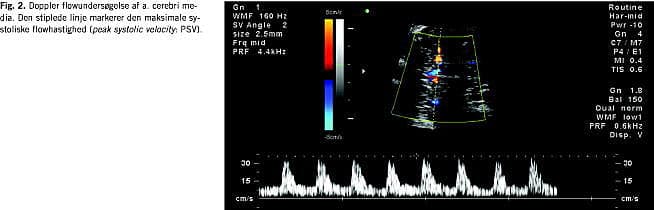

I graviditeter med anæmirisiko for fosteret ønskes viden om fosterets hæmoglobinkoncentration (Hb) som næste trin i udredningen. Niveauet er afgørende for om transfusionsbehandling skal iværksættes eller om igangsættelse af fødslen bør tilrådes, hvis gestationsalderen er fremskreden. Mange metoder har været forsøgt for at opnå denne viden, uden at være nødsaget til at foretage cordocentese med de dertil hørende risici. Antistofniveauet i maters blod giver over en vis cut-off- værdi en dårlig prædiktion af foster-Hb. Hydrops/ascites hos fosteret er meget let at se ved ultralydskanning, men problemet med dette sygdomstegn er, at det forekommer sent i anæmiudviklingen, og at ikke alle fostre udvikler hydrops selv ved meget lav Hb. Endvidere at resultaterne ved behandling af fostre, der allerede er hydrope, når behandling påbegyndes, er klart dårligere end for non-hydrope [3]. Gennem mange år anvendtes monitorering ved at foretage gentagne amniocenteser i løbet af graviditeten med bestemmelse af amnionbilirubin. Værdierne plottedes på et Liley chart, hvor fosterets sandsynlighed/risiko for at blive født med henholdsvis svær anæmi, moderat anæmi eller normal Hb kunne aflæses. Da denne metode er invasiv og ikke så præcis, har mange kliniske forskere forsøgt at finde bedre noninvasive metoder. Bl.a. har følgende været evalueret: miltomkreds, leverlængde, diameter af v. umbilicalis, placentatykkelse og flow indices ved Doppler-undersøgelse af mange forskellige føtale kar [4]. Et gennembrud kom, da man begyndte at måle de maksimale systoliske flowhastigheder (PSV) i a. cerebri media (MCA) (Fig. 1 og Fig. 2 ). Mari et al [5] publicerede i 2000 et multicenterstudie med PSV-MCA og føtal-Hb fra 111 gravide med immunisering og 265 kontroller. Ved retrospektiv analyse fandtes at ved en PSV cut-off -værdi på 1,5 multiplikationer af medianværdien (MOM) og en Hb-cut-off -værdi for transfusionskrævende anæmi på 0,65 MOM fandtes en sensitivitet på 100% og falsk positivrate på 12%. I senere studier med evaluering af MCA-Doppler er der fundet sensitivitet på 88-96% og specificitet på 71-100% [6-8]. Efter 35. uge findes dog en meget høj falsk positivrate [6]. Kontrol med amnionbilirubinbestemmelse er ved mange centre nu erstattet af ultralydkontrol med måling af MCA-PSV.